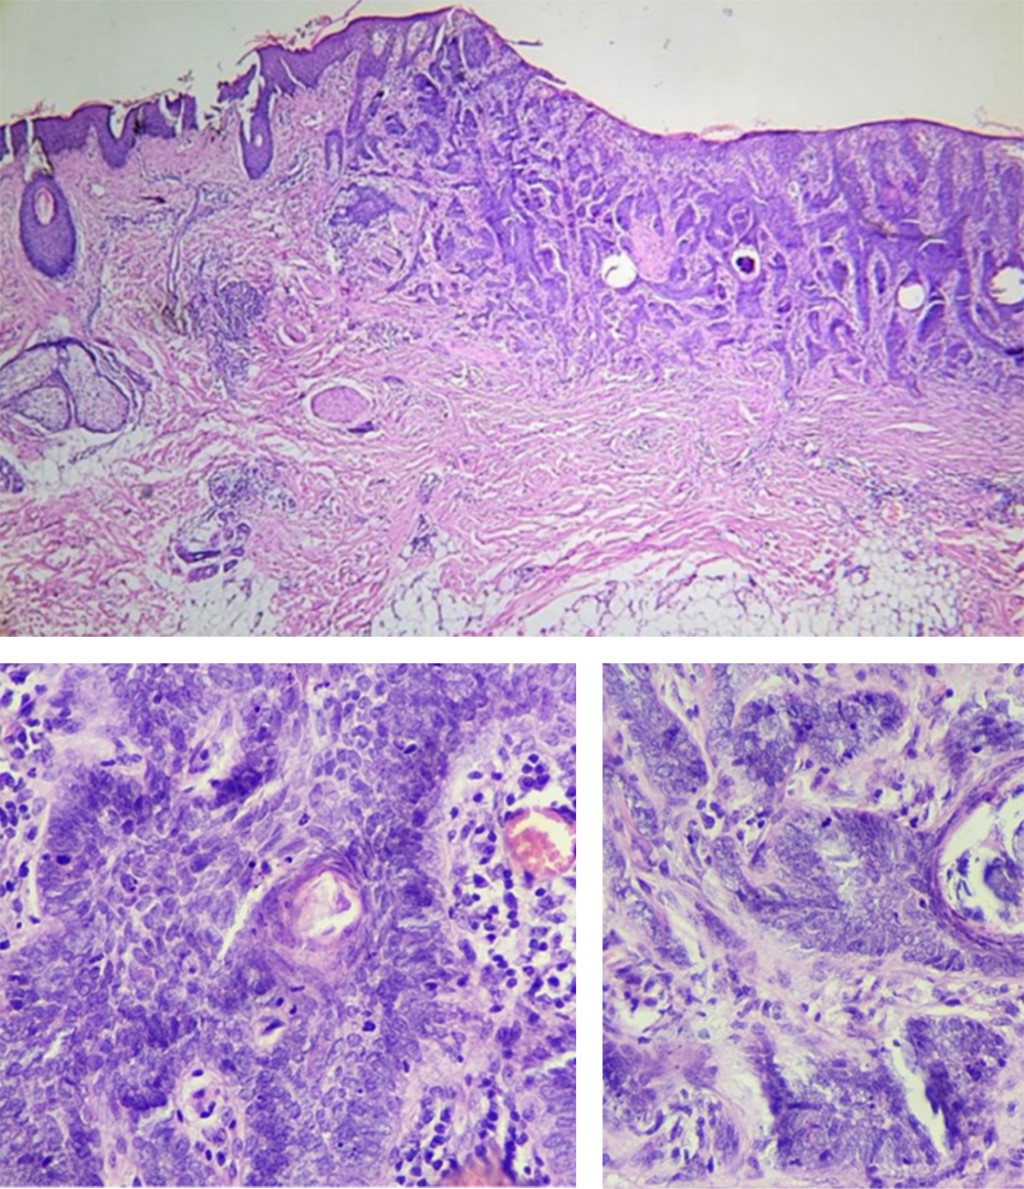

Al tratarse de una niña, sana, sin antecedentes patológicos o familiares relevantes para el caso, se decide realizar tinciones de inmunohistoquímica y consultar un tercer patólogo. Se identifican, en todo el espesor de la dermis, estructuras que forman individualización celular, nidos, cordones y láminas en su centro; se aprecian cavidades microquísticas con diferenciación anexial ecrina, son células pequeñas basaloides y atípicas con citoplasma abundante, eosinófilo con núcleo pleomórfico, con cromatina en gránulos, nucléolo prominente y mitosis atípicas, algunas queratinizan, forman estructuras siringomatoides y cavidades quísticas inmersas en tejido fibroconjuntivo denso esclerótico con vasos sanguíneos dilatados congestivos; infiltración tumoral peri e intramuscular del músculo erector del pelo. El infiltrado inflamatorio está constituido por linfocitos, células plasmáticas y melanófagos. En la hipodermis hay infiltración tumoral focal en escasos racimos (Figura 2).

El diagnóstico es difícil debido a que las biopsias superficiales sólo revelan hallazgos benignos. Histopatológicamente, es pobremente circunscrito y se puede extender a tejido subcutáneo y a músculo esquelético. A la tinción de hematoxilina y eosina, se puede encontrar diferenciación ecrina y folicular. Con una apariencia superficial compuesta por numerosos quistes de queratina que apoyan al origen folicular; y pequeñas islas o cordones de epitelio basaloide y escamoso con diferenciación ductal que pueden invadir profundamente la dermis y que apoyan el origen ecrino. Ambos hallazgos concordantes con el origen de queratinocitos pluripotenciales. El componente más profundo consiste en nidos de células en un estroma hialino y denso. También se encuentra infiltrado subcutáneo, perineural, atipia celular y mitosis específicos de esta neoplasia. Las células cerca de la periferia tienden a elongarse y se disponen en forma de palizada. Los quistes córneos pueden llegar a calcificarse. Hay ductos alineados en dos capas llenos de material eosinofílico positivos al ácido peryódico de Schiff. La presencia de estructuras ductales es lo que la diferencia del tricoepitelioma desmoplásico y tricoadenoma. En inmunohistoquímica, el antígeno carcinoembrionario se tiñe en las estructuras glandulares.2,5,6

La dermatosis de la paciente se presentó en una de las topografías más comunes. Sin embargo, su edad difiere de la reportada en la literatura; además, la morfología probablemente pudo haberse visto modificada por el uso de agentes tópicos. El caso se caracterizó inicialmente por la incongruencia clínico-patológica y, debido a las limitaciones de la biopsia tomada de primera instancia, se tuvo la necesidad de reevaluar la biopsia inicial y consensuar entre patólogos. Los hallazgos comunes histopatológicos coincidieron que se trataba de una neoplasia con células basaloides atípicas, diferenciación folicular, glandular ecrina, quistes córneos y mitosis (Tabla 1).